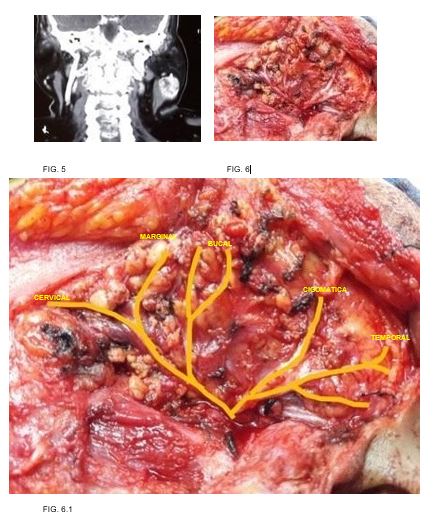

Caso 3: femenino 70 años de edad, antecedente de hipertensión, tabaquismo, diabetes mellitus y dislipidemia, con tumor parotídeo izquierdo de 6cm en su eje mayor, resultando en tumor de Warthin. (FIG. 5-6)

Caso 4: masculino 56 años de edad, antecedente de diabetes mellitus, tabaquismo e hiperplasia prostática, con tumor parotídeo izquierdo de 3cm en su eje mayor, resultando en adenoma pleomorfo. (FIG. 7-8)